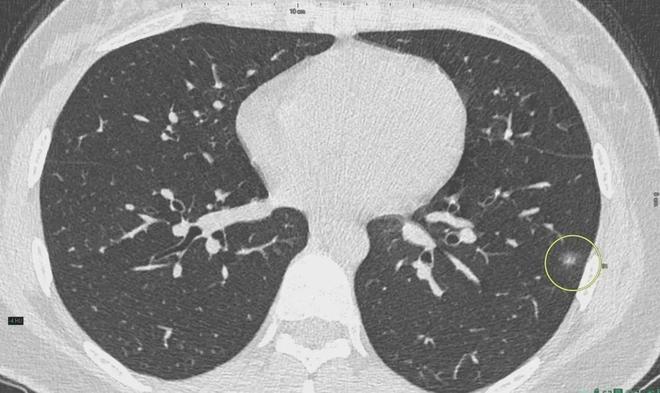

肺結(jié)節(jié)是一種常見(jiàn)的肺部疾病,其發(fā)病率逐年上升,雖然肺結(jié)節(jié)多數(shù)情況下是良性的,但也有可能惡化為肺癌,了解肺結(jié)節(jié)的形成原因?qū)τ陬A(yù)防和治療具有重要意義,本文將為您詳細(xì)解析肺結(jié)節(jié)的形成機(jī)制。